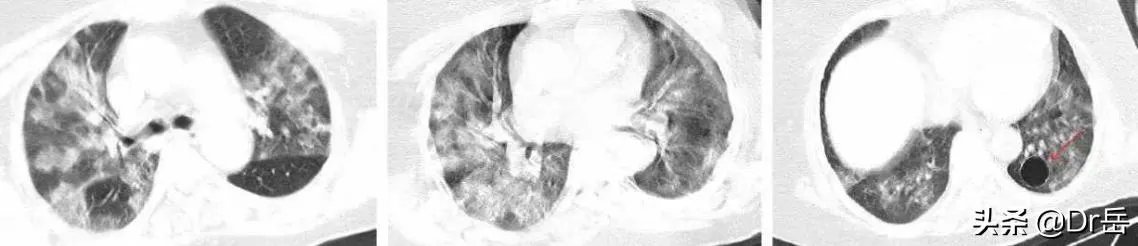

新型冠状病毒肺炎CT表现

临床诊断的好处就是最大程度的避免漏诊。实践是检验真理的唯一标准,很多新型冠状病毒性肺炎患者的核酸检测都是阴性,如果仍然以核酸检测作为标准,那么很多患者都会被漏诊。在这种特殊时期,大面积传染的情况下,选择临床诊断为主,是一个非常明智的选择。

新型冠状病毒肺炎的典型表现是:磨玻璃影和浸润影。钟南山院士的新论文提到,有76%的新冠肺炎病人肺部CT显示典型表现。